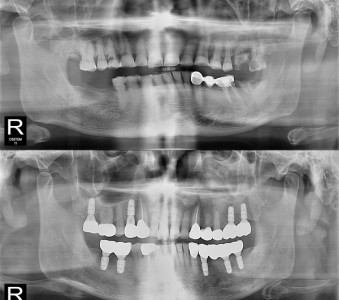

以成果证明实力。

国际摩牙齿科

真实临床案例